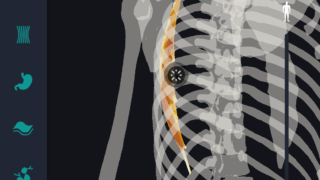

はじめに 本記事では、人体解剖学における専門的な部位の知識を始めに、効果的な勉強法についてご説明します。 人体解剖学では様々な器官や筋肉、骨の名称を覚えるだけではなく、体のどの位置に存在するのかまで覚えなければなりません。そのため、できるだ...